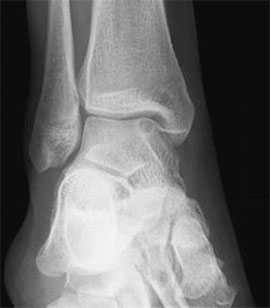

Не смотря на то, что Loomer с соавт. сообщили, что только от 50% до 66% остеохондральных дефектов обнаруживаются при помощи обычной рентгенографии, данный метод является важной отправной точкой и может быть полезен для исключения другой патологии голеностопного сустава [20]. Рентгенологическое исследование голеностопного сустава должно включать переднюю, заднюю и в 3⁄4 внутренней ротации проекции. Все проекции выполняются стоя (под нагрузкой) и называются функциональными. Функциональные рентгенограммы могут быть полезны для выявления сопутствующей нестабильности голеностопного сустава, проекция 3⁄4 во внутренней ротации, помогает в визуализации щели межберцового синдесмоза, а так же отображает передне-внутрений импижмент (таранной и большеберцовой кости) в случае его наличия. Выполненные в положении подошвенного сгибания прямая и 3⁄4 проекция во внутренней ротации могут быть полезны в выявлении заднемедиального поражения таранной кости. Рентгенологические признаки, которые могут быть определены, варьируются от небольших участков сдавления субхондральной кости до крупных отслоенных остеохондральных фрагментов. Радиографическая

Рентгенография

Рутинное рентгенологическое исследование включает рентгенографию обоих голеностопных суставов в прямой и боковой проекциях. На рентгенограммах можно увидеть отслоенный костный фрагмент. Изначально, на начальных стадиях болезни, площадь повреждения может быть очень мала, в связи с чем она не будет видна на рентгенограммах. Иногда изменения становятся видны только при рентгенологическом исследовании в динамике.